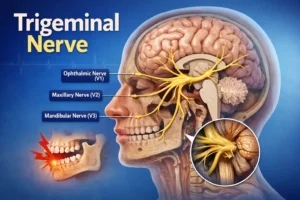

پوسیدگی دندان (Tooth Decay) مشکلی است که در طی آن، مینای دندان تخریب شده و از بین میرود. مینا، لایه بیرونی دندان است که سلول زنده ندارد و وظیفه محافظت از لایههای داخلی دندان را بر عهده میگیرد. دومین لایه دندان هم عاج نام دارد که در پی خرابی مینای دندان، عاج بیدفاع میماند و دندانها نسبت به غذای سرد و گرم حساس میشوند. بخش داخلی دندان هم پالپ نام دارد که حاوی رگهای خونی، اعصاب و بافت همبند دندان است. اگر شدت پوسیدگی زیاد باشد، به بخش پالپ هم میرسد.